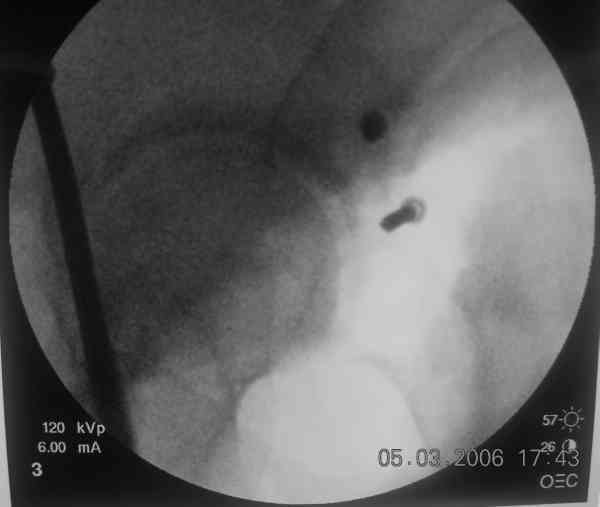

I'll include a few images of a similar injury in a similarly large male patient. This patient "showed up" in our ER c/o hip pain 2 months after being treated in the lateral position, without a quality reduction, without an anterior column transverse supporting implant, with an unbalanced plate applied too medially, with insufficient caudal segment fixation...it took over 8 hours and a 3+ l blood loss to debride the callus from front then

back, excise the HO, release his sciatic nerve, reduce the head-transverse-wall, and fix it...and now it's a staging procedure.

The 2nd example is of a motorcyclist with a transverse fracture-dislocation...he had a closed attempted reduction and placed in traction but the manipulative reduction was not concentric (not unusual for this injury pattern)...so the traction was adjusted to be just enough to disengage the head from the fracture (12#) until he could be cleared for surgery one day after injury...he was treated "urgently" then with a prone KL, clean the fracture, reduce and clamp it, screw it, support with a balanced plate, close, and enjoy...2-3hours, 400cc EBL, blah, blah, blah..